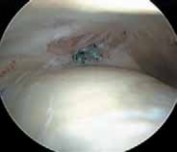

Indiscriminate débridement of the ligamentum teres should be avoided and intact fibers preserved; however, débridement of the disrupted portion can be quite beneficial ( TECH FIG 4).

Most of the contents of the acetabular fossa are best accessed from the anterior portal.

9.

However, a portion of the posterior contents often is best accessed with instrumentation introduced from the posterolateral portal.

10.

Between these two sites most pathologic processes can be accessed with combinations of straight, curved, and flexible instruments.

). B. Débridement is begun with a synovial resector introduced from the anterior portal. C. The acetabular attachment of the ligamentum teres in the posterior aspect of the fossa is addressed from the posterolateral portal. (Reprinted with permission from Byrd JWT, Jones KS. Traumatic rupture of the ligamentum teres as a source of hip pain. Arthroscopy 2004;20:385–391.) PEARLS AND PITFALLS Patient selection Patient positioning Portal placement Avoid iatrogenic damage Avoid excessive labral resection Avoid advanced disease states